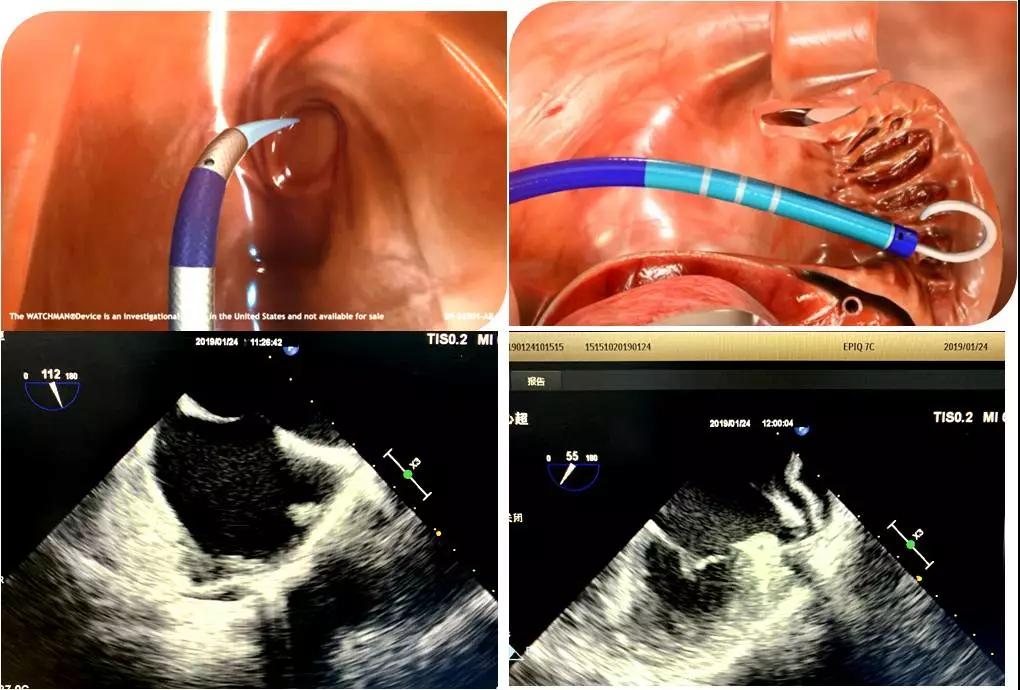

于2019年1月24日上午,心内科主任马锋、副主任医师潘军强在介入室对一例房颤患者进行左心耳封堵术,超声科郑瑜主任为该患者实施了术中经食管超声心动图监测,清晰显示了房间隔的穿刺,并多平面多角度测量左心耳的超声径线,监测鞘管进入左心耳根部,展开与释放封堵器,并及时评估了封堵器的最终位置、稳定性等,经食道超声的“慧眼“监测为该心脏手术的顺利进行提供了有力保障。